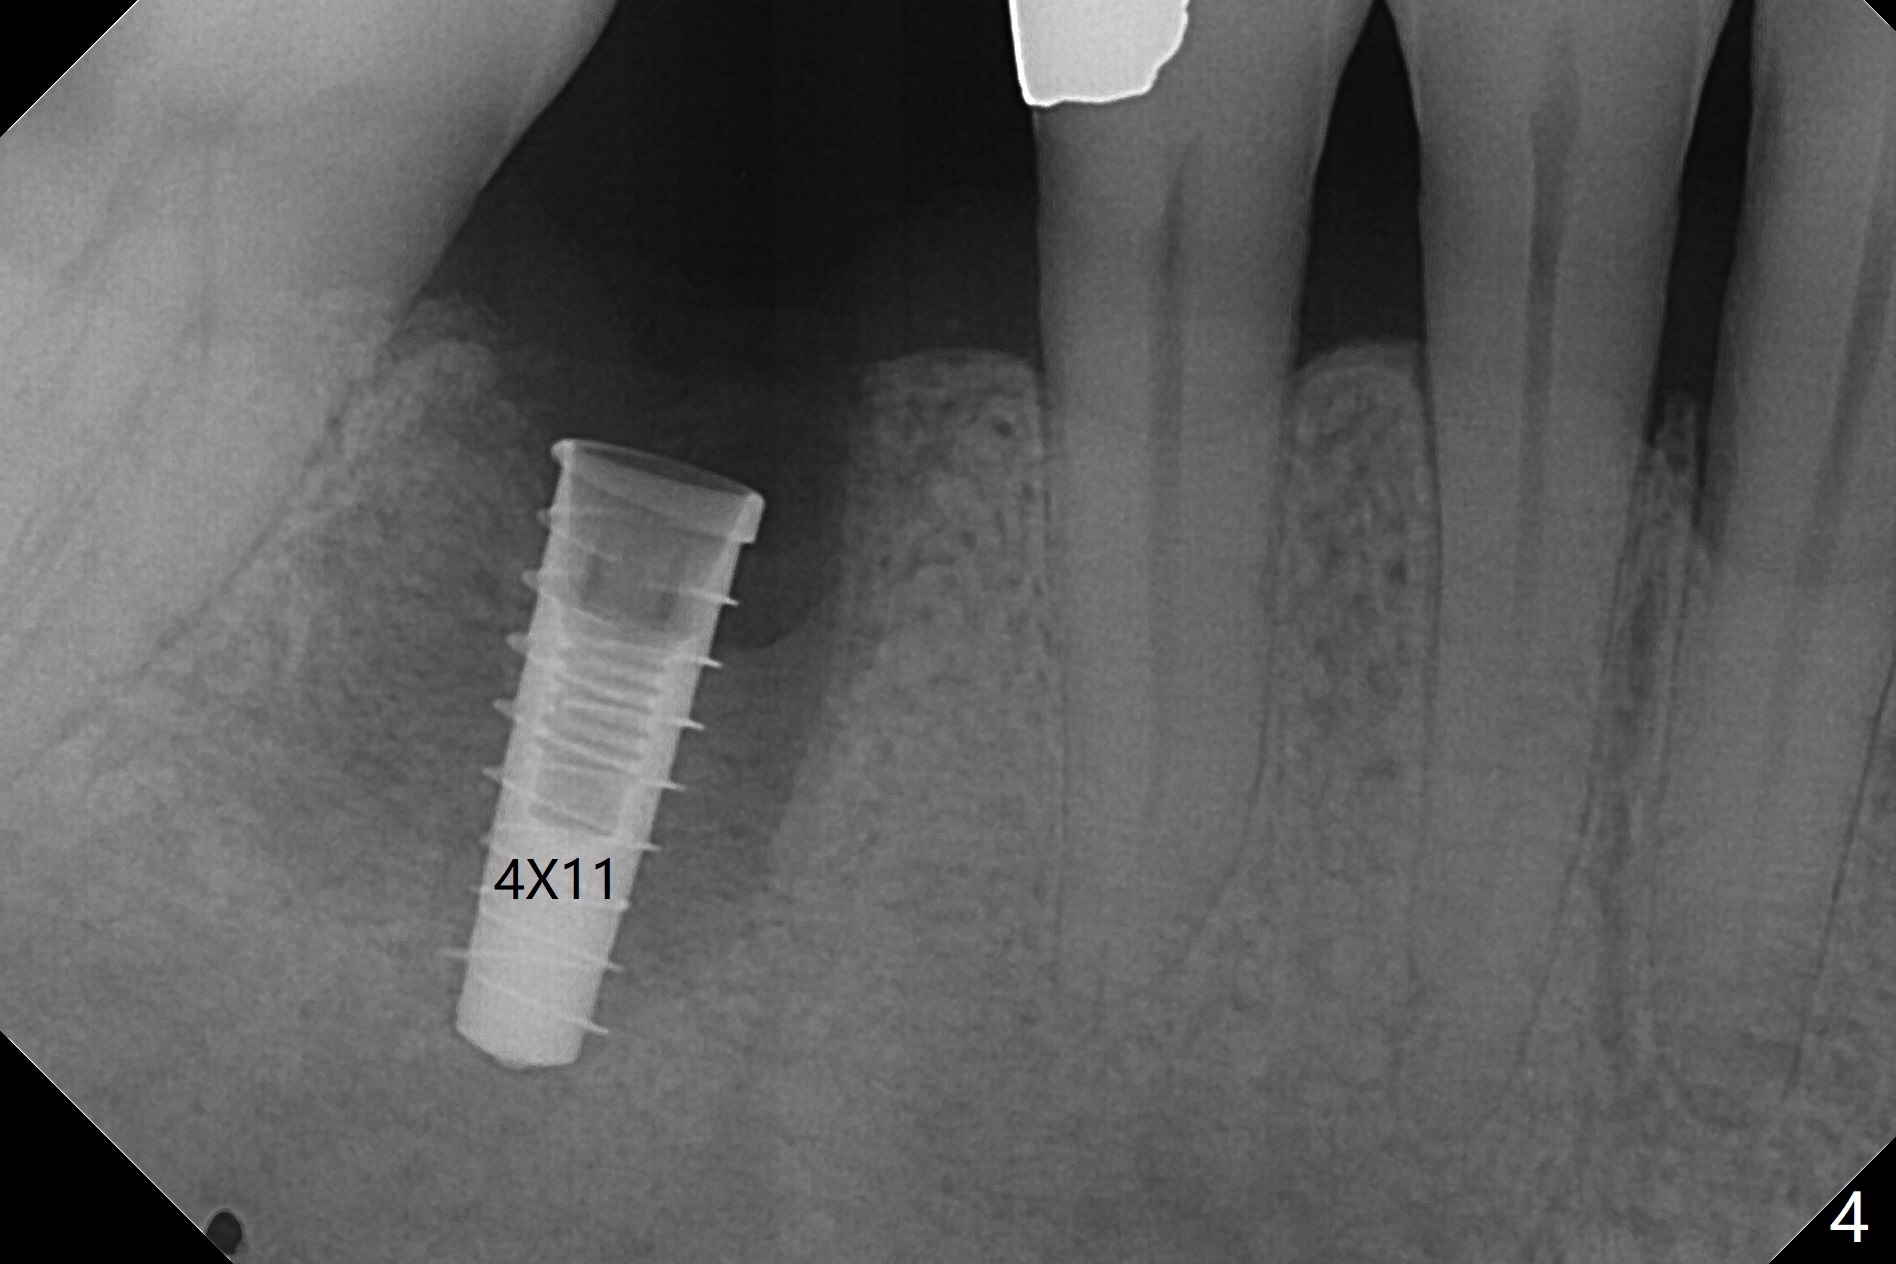

As planned, the crown of the tooth #30 with lingual (Fig.1 L) caries is removed and flattened with surgical handpiece so that the guide is able to be seated without interference. The osteotomy by 10.5 mm offset bone trimmer is lingual (Fig.2 white circle; due to in part the lingual caries and in part design error); in order to let the osteotomy to bounce back buccal, the part of the buccal roots are removed by surgical bur (arrows). The initial osteotomy by 2.2 mm drill is in the middle of the septum (Fig.3). After the last drill (3.5x11.5), the remaining roots are easily removed with proximators; a 4x11 mm dummy implant is placed with low stability and supracrestal lingual (Fig.4). Therefore a 4.5x9 mm final implant is placed with low torque. Following 4x11.5 mm drill, the torque increases to 20 Ncm. With insertion of healing screw, sticky bone (Fig.4 *: .5-1 mm cortical/cancellous allograft) is heavily packed around the implant (arrow), which apparently allows removal of the healing screw and placement of a 6x5.7(3) mm pair abutment without loosening the underlying implant. More bone graft is placed (Fig.6), followed by 2 pieces of PRF membranes. Although the implant is slightly buccally placed (Fig.7, due to over-removal of the buccal root, Fig.2 arrows), it is placed in the septum (Fig.8 S). To further compensate for the low implant stability, setting acrylic is applied in the edentulous area, particularly into the undercuts of the neighboring teeth (Fig.9 *) and around the abutment. The lingual margin of the acrylic dressing is extended (Fig.10 arrow) to cover the soft tissue defect associated with the lingual caries. As compared to the design (4x10 mm, Fig.11), the implant (4.5x9 mm, Fig.12) is placed buccal and ~ 2 mm deeper, reducing the chance of periimplantitis. The acrylic dressing is in place, but has mobility. The gingiva is healthy 2 weeks postop. The dressing is removed 1 month postop; the socket heals around the abutment buccal (Fig.13) and lingual (Fig.14). In spite of the immediate provisional, the abutment margin is substantially subgingival mesial 4 months postop, extremely difficult to take impression. A smaller diameter and longer cuff abutment is placed (Fig.15). The lingual gingiva heals normal 5 months postop, immediately before cementation (Fig.16).